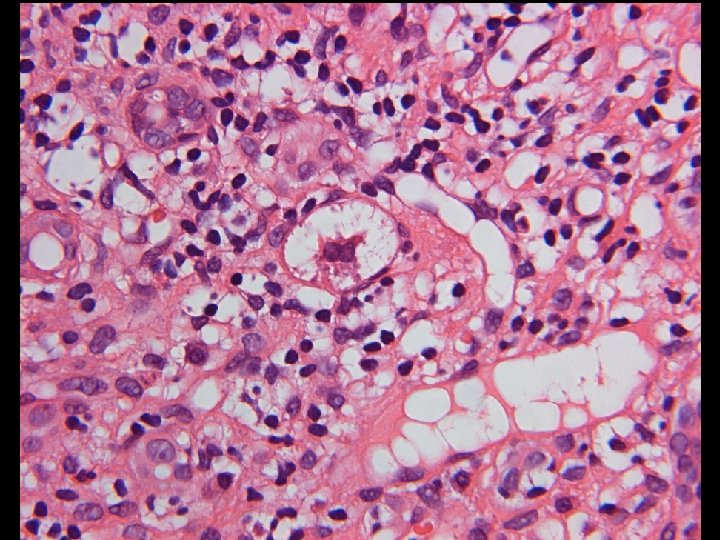

Diagnose einer NASH (Mindestkriterien) • Überwiegend makrovesikuläre, Läppchenzentren betreffende Steatose, die im Stadium der Zirrhose aber verschwinden kann; • Milde Infiltration des Leberparenchyms durch neutrophile Granulozyten und Rundzellen; • Ballonierung der Hepatozyten.

Zusatz-Kriterien für NASH • • • Mallory-Hyalin Glykogen-Lochkerne Perisinusoidale Fibrose der Zone 3 Megamitochondrien (Adoleszenten) portale lymphozytäre Entzündung.

Tabelle 3. NASH Clinical Research Network Scoring System (II) Fibrose (mit Masson´s Trichrom-Färbung) 0: Keine 1 a: Leichte Zone 3 perisinusoidale Fibrose, nur bei Trichrom Färbung zu sehen 1 b: Mäßige Zone 3 perisinusoidale Fibrose, kann gesehen werden mit H&E 1 c: Nur portale Fibrose 2: Zone 3 perisinusoidale Fibrose und periportale Fibrose 3: Verbrückende Fibrose 4: Zirrhose